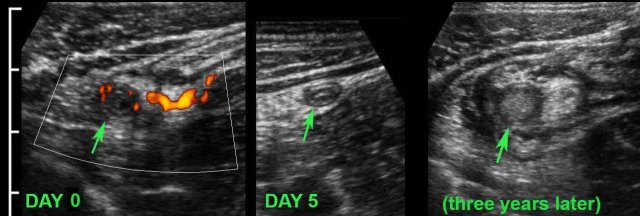

This young woman had pain in the RLQ for 24 hours (WBC 12, CRP 34), when she noticed rapid resolution of symptoms.

US showed a small 6.5 mm hyperemic appendix (arrow), surrounded by inflamed fat.

She was not operated and was symptom free the next day.

US after 5 days showed normalization of the appendix (arrow).

Three years later, she had recurrent symptoms and US showed acute appendicitis.

Surgery revealed perforated appendicitis.